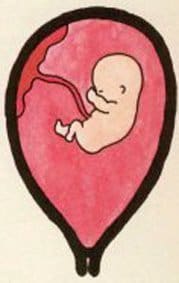

Durante il terzo mese, l’embrione acquisisce un aspetto umano, cambia nome e diventa il feto. In questa 4 settimane il feto assumerà sempre di più l’aspetto di un neonato. La testa è sempre molto grossa ma il corpo diventa più ...

Gli organi del feto continuano a svilupparsi durante il terzo mese di gestazione, alcuni si mettono in funzione e danno un po’ più d’autonomia al bambino: ...

Durante il mese precedente, la circolazione sanguigna non era in grado di essere autonoma in quanto l’embrione non poteva produrre cellule sanguigne. ...

Ecco quanto spazio occupa il vostro bambino al terzo mese di gravidanza. ...